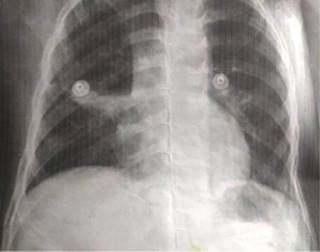

Estudios: difusión de monóxido de carbono (DLCO) 7.5 mL/min/mmHg (valor predicho 10.2), espirometría posbroncodilatador con una respuesta en volumen espiratorio forzado en el primer segundo (FEV1) del 16% y de más de 200 mL. La radiografía de tórax muestra un patrón atelectásico (Figura 1). Serie esofagogastroduodenal (SEGD) con presencia de reflujo grado III; en la angiotomografía de tórax (angio-TC) se observa una subclavia derecha aberrante (Figura 2), lo mismo que en la aorta descendente, también un vaso aberrante (Figuras 3 y 4).

Figura 1: Telerradiografía de tórax: presenta una imagen que incrementa la densidad pulmonar en el lóbulo medio caracterizada por un patrón de consolidación con broncograma aéreo y signo de silueta positivo, sugerentes de una atelectasia pulmonar.